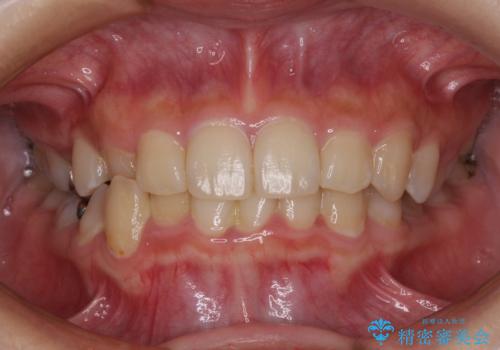

30代女性 前歯のがたつき